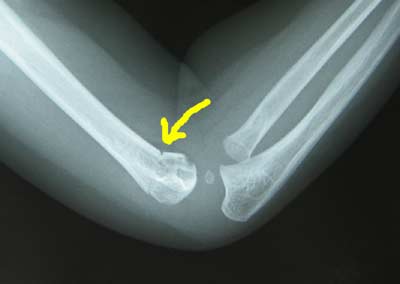

看護師さんにお願いし、息子のレントゲン写真を見せてもらうことに。

研修の先生を呼んで頂き、説明を受ける。

神経を圧迫すれば痛むだろうし、血管を傷つけていれば腫れ上がる。

どちらも全く見られず、本人にも痛みはないだろう。

全く不幸中の幸いであった、との事。

![]() |

矢印の先、 黒く凹んでいるのがわかるでしょうか。 折れているんだそうです。 |